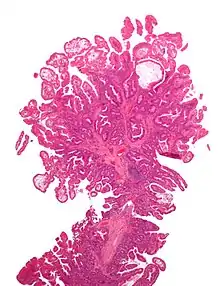

Micrograph of a Peutz–Jeghers colonic polyp – a type of hamartomatous polyp. H&E stain.